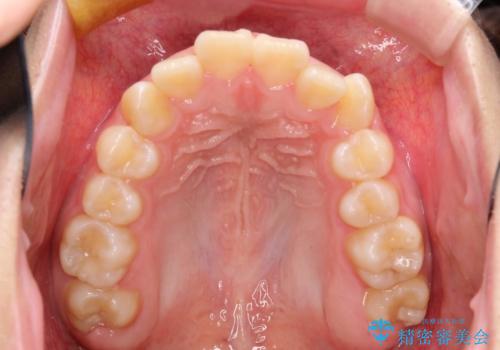

抜歯矯正で口元に変化を ラビアル・ワイヤー矯正でEライン

- 上下左右4本の小臼歯を抜歯、ラビアル・ワイヤー矯正を計画した。

抜歯をして第1小臼歯分のスペースを獲得することにより、ガタつきの改善と前歯のリトラクトをおこない、横顔の印象もすっきりとし、整ったEラインを作ることができました。